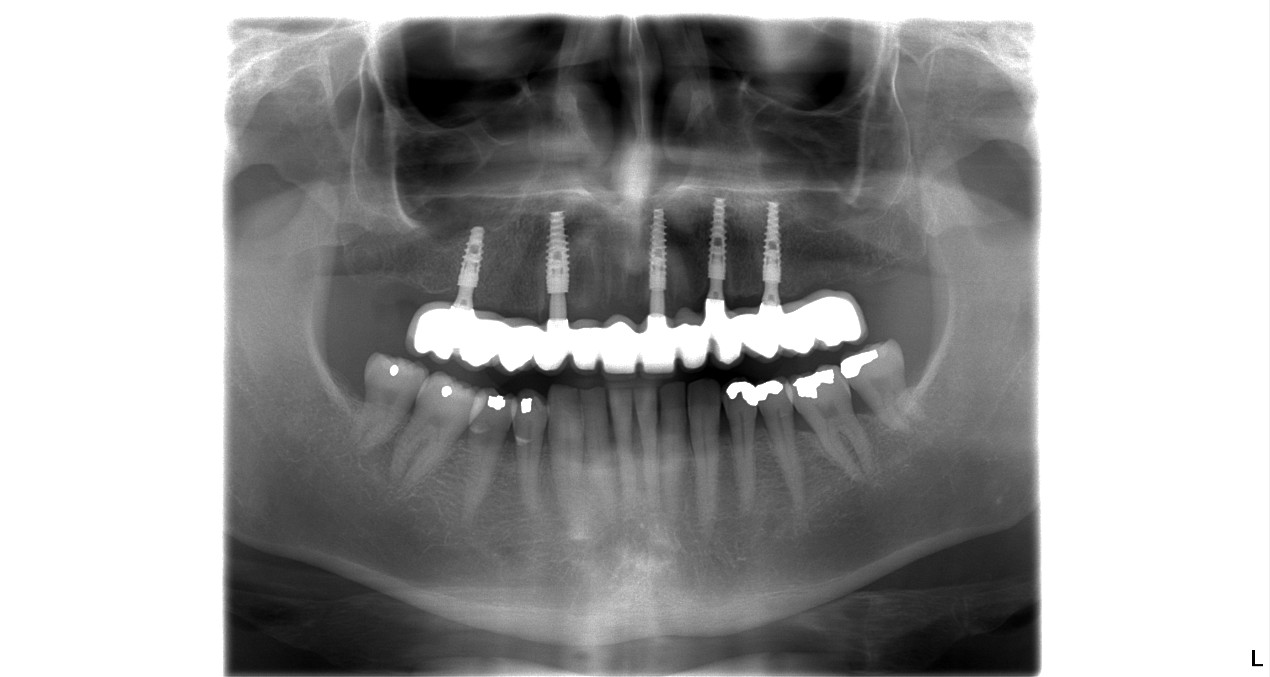

After his initial dental consultation done on the day of his 1st visit to us, our implantologist Dr. Marek prepared a personalized treatment plan for John, which included a 12 unit ceramic bridge fitted on 5 dental implants.

See the immediate change after first visit.